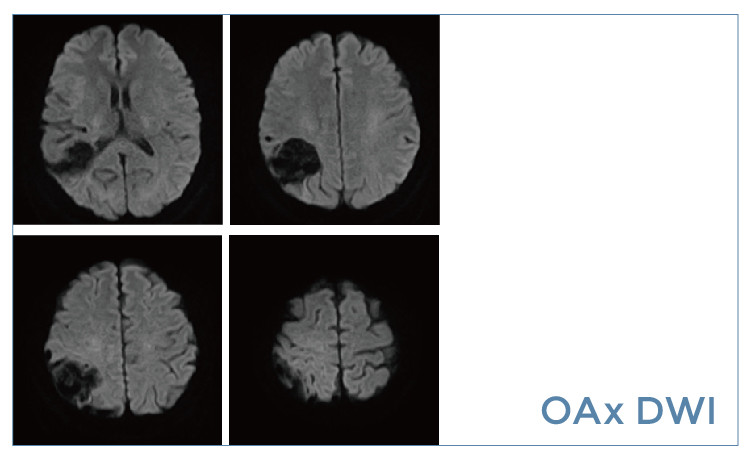

【朗润影像档案】20190531磁共振影像病例结果讨论